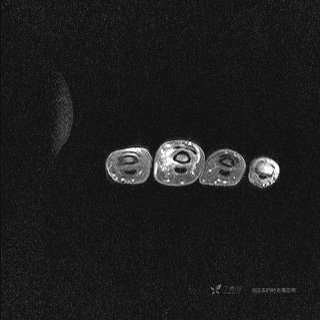

DWI ADC

提示:小指是伪影。